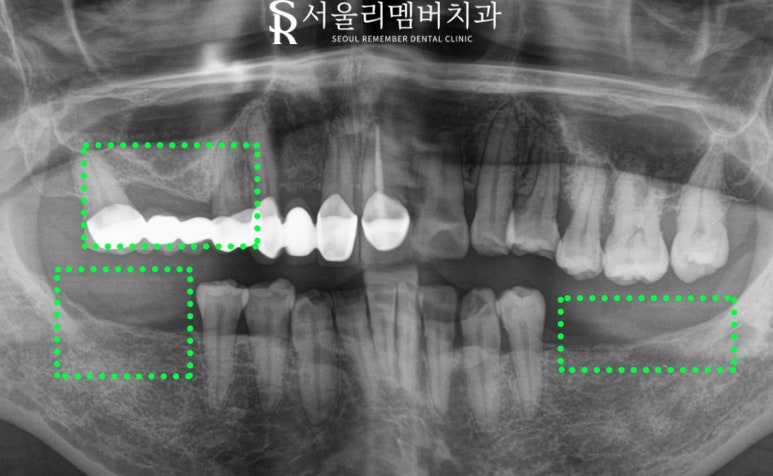

진단

낙성대 치과 에서 꼼꼼하게 진단한 결과

표시해 둔 곳은 임플란트를 진행해야 됩니다.

쉽게 정리해 드리면

#15,17,35,37,46,47 은 임플란트

#11,13,14,25,26,27은 신경치료로

아픈 구강 해결해 드리기로 했습니다.